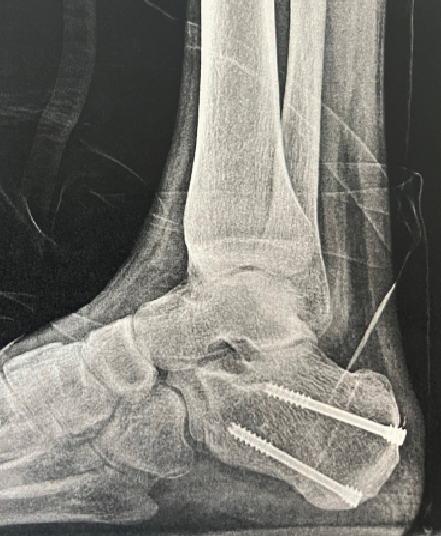

The surgical plan included a talectomy with calcaneonavicular arthrodesis, a fibular osteotomy and resection with utilization of allograft and autograft with bone marrow aspirate. Grafting back-filled any residual non-contact sites at the arthrodesis. Finally, multiple 3.5mm screws were utilized for the fusion (Figure 3).